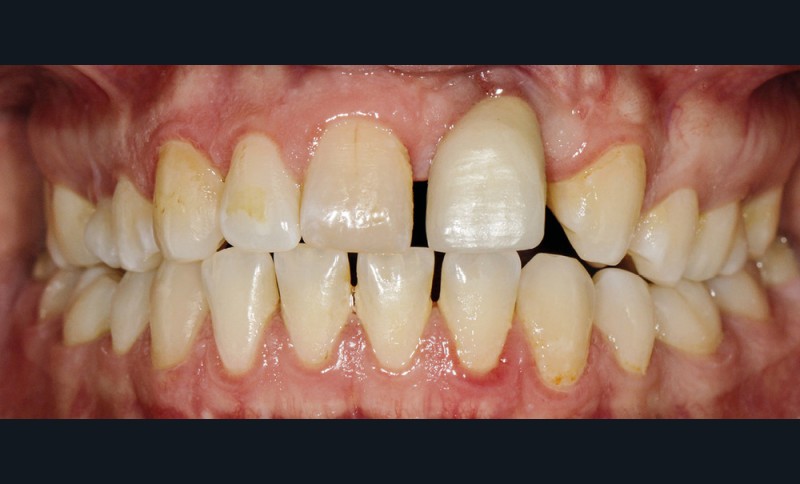

- au niveau dentaire : une arcade maxillaire asymétrique avec déviation du milieu maxillaire à gauche. On note l’absence de 21, 22, 25, 35 et 45, une classe II droite et gauche avec infraclusion antérieure et la présence d’un implant en place de 21 avec un diastème de 3 mm entre 21 et 23 (fig. 3) ;